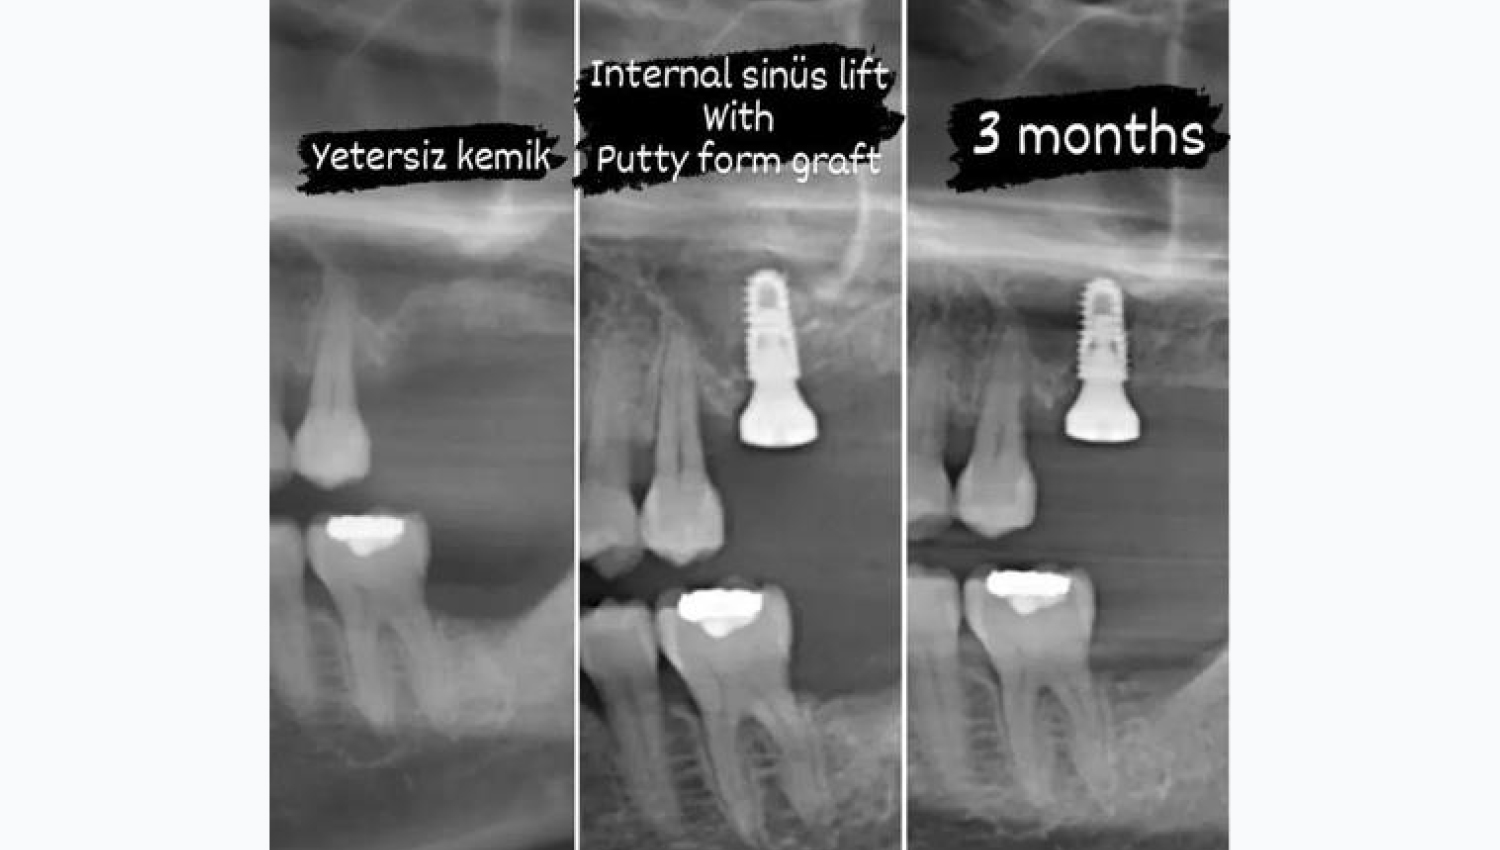

- Female, 42 years old.

- Internal sinĂ¼s lift with Powerbone Dental

- Putty.

- Case performed by Dr. Alparslan Burak , TR

1.Initial radiological view.

2.Crestal sinus lift with modificated technique using Powerbone Dental Putty.

3. 4-month follow-up radiological imaging after implantation. The advantage of this technique is that in the internal sinus lift, it allows the sinus to be pushed more than 3 mm safely and allows a longer implant to be placed at the same time.

5.Comparison of radiological images.